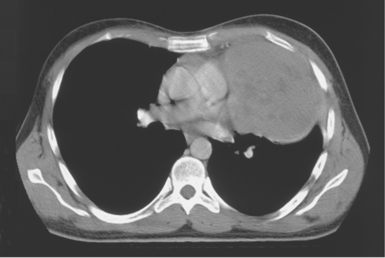

Blood travels to and from the heart through the great vessels, which include the aorta, pulmonary arteries and veins, and superior and inferior venae cavae (Figures 6.54 and 6.55). The aorta is the largest artery of the body and can be divided into the ascending aorta, aortic arch, and descending aorta. The ascending aorta begins at the base of the left ventricle at the level of the sternal angle, then curves superiorly and posteriorly as the aortic arch over the root of the left lung. The top of the aortic arch is approximately at T3 (Figures 6.56 and 6.57). The arch continues as the descending aorta posterior to the left bronchus and pulmonary trunk, on the left side of the vertebral body of T4 (Figures 6.58 and 6.59). The descending aorta passes slightly anterior and to the left of the vertebral column as it descends through the thoracic and abdominal cavities (Figure 6.60). While in the thoracic cavity, the descending aorta is commonly called the thoracic aorta, and while in the abdominal cavity, it is called the abdominal aorta. The pulmonary trunk is the origin of the right and left pulmonary arteries and lies entirely within the pericardial sac. It arises from the right ventricle and ascends in front of the ascending aorta, courses posteriorly and to the left, where it bifurcates at the level of the sternal angle (T4) into the right and left pulmonary arteries (Figures 6.61 through 6.63). The pulmonary trunk is attached to the aortic arch by a fibrous cord called the ligamentum arteriosum, the remnant of an important fetal blood vessel (ductus arteriosus) that links the pulmonary and systemic circuits during fetal development (Figures 6.54 and 6.61). The right pulmonary artery courses laterally, posterior to the ascending aorta and superior vena cava, and anterior to the esophagus and right mainstem bronchus, to the hilum of the right lung. At the root of the right lung, the right pulmonary artery divides into two branches, with the lower branch supplying the middle and inferior lobes and the upper branch supplying the superior lobe (Figures 6.61 through 6.64). The left pulmonary artery, shorter and smaller than the right, is also the most superior of the pulmonary vessels. It travels horizontally, arching over the left mainstem bronchus, and enters the hilum of the left lung just superior to the left mainstem bronchus (Figures 6.61 through 6.64). Within the lungs, each pulmonary artery descends posterolateral to the main bronchus and divides into lobar and segmental arteries, continuing to branch out and to follow along with the smallest divisions of the bronchial tree (Figures 6.61 and 6.64). Located inferior to the pulmonary arteries are the four pulmonary veins, two each (superior and inferior) extending from each lung to enter the left atrium (Figures 6.54, 6.55, 6.61, and 6.64 through 6.68). They commence in a capillary network along the walls of the alveoli, where they are continuous with the capillaries of the pulmonary arteries. The venous capillaries merge to form small vessels that unite successively to eventually form a single trunk for each lobe: three for the right and two for the left lung. Frequently the trunk from the middle lobe of the right lung unites with the trunk from the upper lobe, forming just two trunks on the right side prior to entering the left atrium. The right superior pulmonary vein collects blood from the upper lobe segments of the right lung and passes anterior and inferior to the right pulmonary artery, behind the superior vena cava. The right inferior pulmonary vein receives blood from the right lower lobes of the lung and crosses behind the right atrium to the left atrium (Figures 6.61 and 6.69 through 6.71). The left superior pulmonary vein receives blood from the left upper lobe of the left lung and courses anterior and inferior to the left main bronchus as it enters the left atrium. The left inferior pulmonary vein drains the inferior lobe of the left lung and passes toward the left atrium anterior to the bronchi (Figures 6.61 and 6.72 through 6.74). The pulmonary veins course more horizontally than the pulmonary arteries and are ultimately oriented toward the left atrium. At the root of the lungs, the pulmonary veins are anterior to the pulmonary arteries, which are anterior to the bronchus. While within the lungs, the branches of the pulmonary arteries are anterior to the bronchi, which are anterior to the pulmonary veins. The superior and inferior venae cavae are the largest veins of the body. The superior vena cava is formed by the junction of the brachiocephalic veins, posterior to the right first costal cartilage, and carries blood from the thorax, upper limbs, head, and neck (Figure 6.24). As it travels inferiorly, it is located posterior and lateral to the ascending aorta before entering the upper portion of the right atrium (Figures 6.54 through 6.59). The inferior vena cava is formed by the junction of the common iliac veins in the pelvis and ascends the abdomen to the right of the abdominal aorta and anterior to the vertebral column. It passes through the caval hiatus of the diaphragm and almost immediately enters the inferior portion of the right atrium (Figures 6.75 and 6.76).

Figure 6.59 Axial CT scan of chest with ascending and descending aorta.

Key: SVC, Superior vena cava; asa, ascending aorta; da, descending aorta; ca, carina;